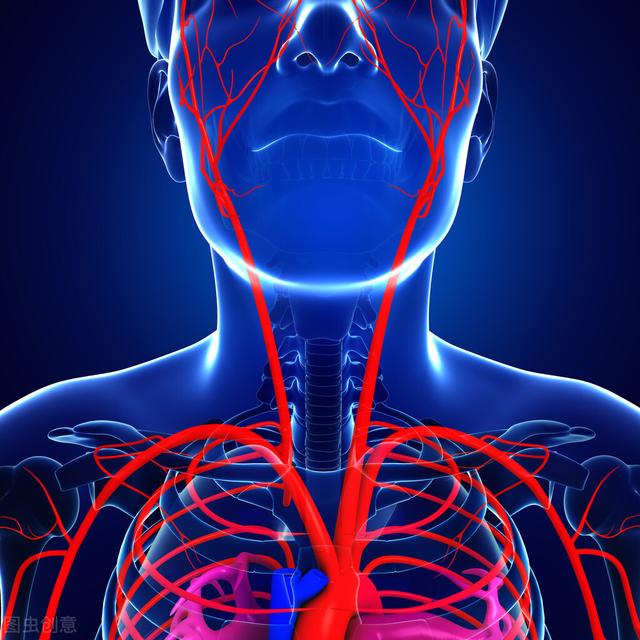

(1) 頸動脈はどこにあるのか?頸動脈は首の前方、気管のすぐ脇にあります。気管の位置は誰もが知っているとおり、首のちょうど真ん中あたりで、硬いところを感じることができる。頸動脈は心臓の動脈に非常に近いため、頸動脈に触れることで、心臓がまだ拍動していないことを知ることができる。頸動脈の拍動を自分で感じることもできます。しかし、特に強く押す場合は、両側を同時に感じないようにしてください。

(2) 頚動脈の役割は?総頸動脈は心臓から頭部への血液供給の橋渡し役であり、中間経路です。 頸動脈が閉塞すると頭部への血液供給ができなくなります。頸動脈が高い位置にある場合、頸動脈は内頸動脈と外頸動脈という2つの大きな枝に分かれます。

まず、頸動脈の閉塞を十分に理解するために、頸動脈の基本的な知識を知っておく必要があります。頸動脈は首の前の気管の両側にある2本の太い動脈で、一般的に血管を高速道路に例えると、頸動脈は脳への2本の高速道路で、主に脳の前に血液と酸素を供給する役割を担っています。従って、通常であれば、頸動脈が閉塞すると、身体の最も強い反応は脳の主要な中心部分となるはずである!

頸動脈図

上の写真によると、我々は明らかに頸動脈は首の非常に重要な血管であることを知ることができ、首の喉頭結節の隣に2本の横指は、そのブールに触れることができ、ちょうど動脈を発行し、総頸動脈と呼ばれ、総動脈の両側は、胸鎖関節の後、気管と喉頭の外側に沿って上方気管と喉頭の外側に沿って平坦に甲状軟骨の上端に、内頸動脈と外頸動脈に分かれている、総頸動脈の頭部、顔面、頸部出血圧迫。

まず、基本的なことを知っておく必要がある。頸動脈は頸部の非常に重要な血管で(図のように)、喉頭結節の横の頸部で2本の横指をそのブーイングに触れることができ、ちょうど総頸動脈として知られている動脈を発行し、気管と喉頭の外側に沿って上方気管と喉頭の後ろの胸鎖関節を通って総動脈の両側、甲状軟骨の上端の平坦部に内頸動脈と外頸動脈に分かれて、頭部と顔面、総頸動脈を押したときに頸部の出血は、血流を止めるために一時的な応急処置に使用することができます。ここを触って、心拍があるかどうかを調べることができます。

頸動脈の基礎知識

内頸動脈は、心臓と脳を結ぶ血液供給の橋渡し役として、私たちの体にとって非常に重要である。外頸動脈は主に頭部、顔面、頸部に血液を供給していますが、上甲状腺動脈も総頸動脈から供給されています。総頸動脈がいったん閉塞すると、内頸動脈と外頸動脈から血液を供給されている部位は血液供給を失い、虚血性変化を起こす。